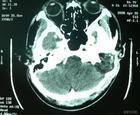

小腦出血

(一)小腦出血(cerebellar hemorrhage) 起病突然,首發症狀為頭痛、嘔吐等急性顱壓增高症狀及眩暈。多數患者起病時意識清楚,出現共濟失調步態,少數患者突然出現癱瘓。瞳孔正常或較小,兩側可以不對稱。兩眼共同凝視,多向病灶對側,少數患者出現眼球震顫。小腦出血的診斷依據為:突然發病,出現嘔吐、肌張力低、蟬孔小或兩側不對稱,角膜反射遲鈍或消失。